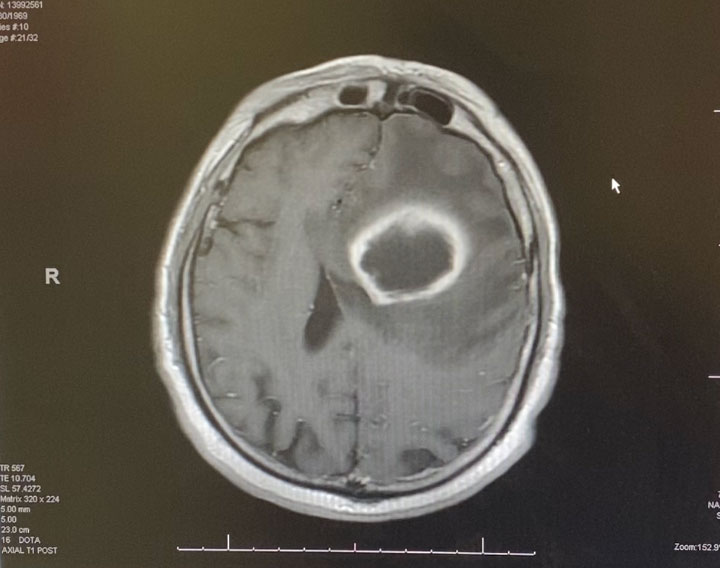

Pre-treatment axial post contrast MRI

Image 1: Pre-treatment axial post contrast MRI.

This is a 50 year old man who last year had undergone gastrectomy for gastric cancer. He presented now with new onset of lethargy and aphasia, with both a receptive and expressive component . He was also experiencing intermittent bradycardia. Brain imaging showed a 3 cm ring enhancing , fluid filled mass in the left frontal region with significant surrounding edema, mass effect, and midline shift. (Image 1 shows axial post contrast MRI. ) Recent imaging of the body had shown no evidence of active metastatic disease.